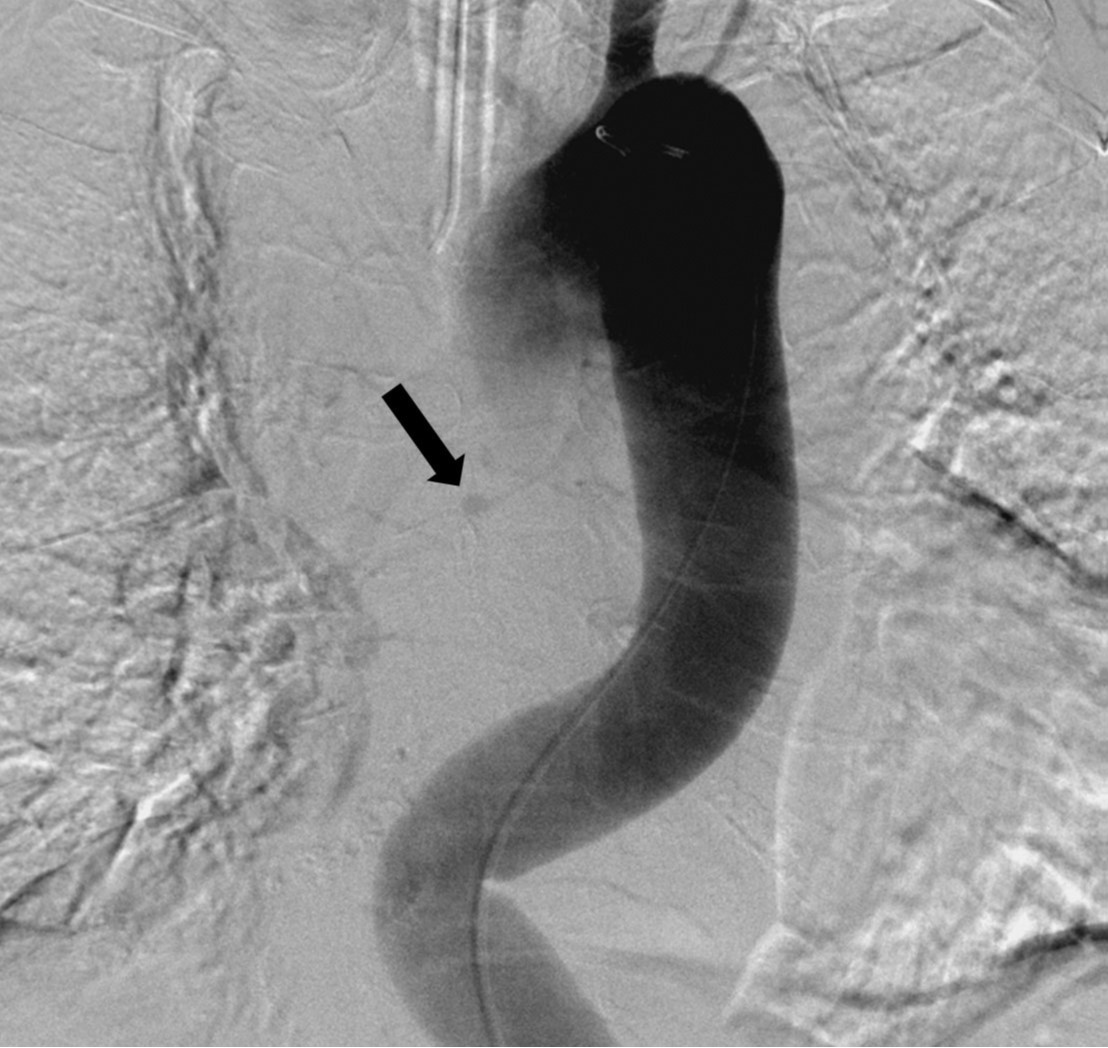

우총대퇴동맥을 통해 5F sheath를 삽입하였다. 5F flush catheter를 대동맥궁에 위치시켜 대동맥조영술을 시행하였고, 대동맥조영술에서 흉부 정중앙에 둥근 모양의 동맥류로 추정되는 병소가 관찰되었음(Fig. 3A). 5F bronchial catheter를 이용해 선택적 우기관지동맥조영술을 시행하였고, 우기관지동맥의 중간 부분에 위치한 동맥류를 확인할 수 있었음(Fig. 3B). 2.0F Progreat microcatheter(Terumo, Tokyo, Japan)를 이용하여 우기관지동맥 동맥류의 원위부까지 진입하였고, 총 9개의 3mm x 2cm Tornado coil(Cook, Bloomington, USA)을 이용하여, 동맥류의 원위부부터 근위부까지 색전을 시행하였다. 색전술 중 동맥류로 추정되는 병소로부터 조영제 유출이 있었고, 코일의 일부가 파열된 동맥류로 돌출하는 것을 볼 수 있었다(Fig. 4). 이후 우기관지동맥의 근위부에서 gelfoam을 이용하여 추가로 색전술을 시행하였다. 이후 시행한 선택적 우기관지동맥조영술 및 대동맥조영술에서 동맥류의 완전 차단과 더 이상의 조영제 유출이 없는 것을 확인하였다(Fig. 5)

Fig. 3A, B. Thoracic aortogram (A) shows a small aneurysm (arrow) in the mid-thorax. Common bronchial arteriogram (B) reveals that the aneurysm (arrow) is located at the mid-portion of the right bronchial artery (arrowheads).

Fig. 3. B